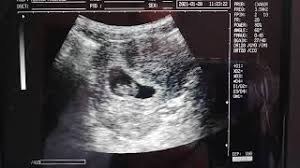

Para la mayoría de los obstetras la semana 8 de embarazo es el momento idóneo para realizar los primeros análisis de sangre y orina y así descartar cualquier complicación relacionada con alguna enfermedad también se han podido llevar a cabo la semana anterior. En la semana 8 de embarazo es prácticamente el comienzo del embarazo. Por otra parte la mujer puede notar que su barriga ha crecido un poco o sentir la ropa ajustada con 8 semanas aunque esto no es evidente en todos los casos.

Pruebas durante la semana 8 de embarazo. Y la madre nota de lleno muchos signos del primer trimestre. No obstante tu cuerpo está cambiando y no tardarás en notar algunos síntomas molestias derivados de tu nuevo estadoGeneralmente en estas fechas se suele pedir cita con el especialista y en ella se puede realizar la primera ecografía para determinar la fecha probable.

Ahora mismo su tamaño es de unos 20 mm.

Ya deberías haber contactado con tu obstetra. En la semana 8 se empieza a formar la piel del embrión que es translúcida y. Y la madre nota de lleno muchos signos del primer trimestre. Semana 8 de Embarazo Síntomas Cuidados Panza y Ecografía La octava semana de embarazo obstétrica corresponde a la sexta semana embrionaria. Normalmente en la sanidad pública se realizan tres análisis. En la semana 8 de embarazo aún estamos en el segundo mes. Evolución detallada del bebé con su tamaño longi. Pruebas durante la semana 8 de embarazo. Y parece un frijolito saltarín porque no para de moverse y cambiar de posición aunque todavía es pronto para que sientas esta actividad.